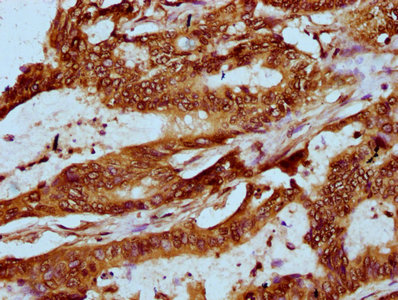

IHC (Immunohiostchemistry)

(IHC image of AAA235142 diluted at 1:20 and staining in paraffin-embedded human colon cancer performed on a Leica BondTM system. After dewaxing and hydration, antigen retrieval was mediated by high pressure in a citrate buffer (pH 6.0). Section was blocked with 10% normal goat serum 30min at RT. Then primary antibody (1% BSA) was incubated at 4 degree C overnight. The primary is detected by a biotinylated secondary antibody and visualized using an HRP conjugated SP system.)